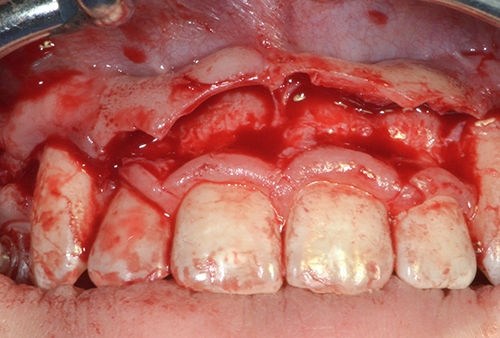

Diş tacının cərrahi uzadılması müxtəlif kliniki hallarda müxtəlif məqsədlərlə tətbiq edilən cərrahi müalicə prosedurudur. Bu metod estetik stomatologiyada “Gummy smile” (diş əti gülüşü) olaraq adlandırılan durumun ortadan qaldırılması məqsədilə geniş tətbiq olunur. Bu zaman kliniki hala bağlı olaraq bəzən yalnız diş əti, bəzən isə həm diş əti həm də sümükdən müəyyən miqdarda rezeksiya edilməklə (kəsilməklə) diş və diş ətinin estetik cəhətdən ideal görünüşü əldə olunur.

Bundan başqa, travma, ciddi karioz zədələnmə, normadan artıq preparasiya (diş yonulması) və s. nəticəsində diş tacının böyük ölçüdə dağılması zamanı bu dişlərin üzərinə qapaq, körpü konstruksiyalarının hazırlanması və ya bu dişlərin çıxan diş konstruksiyaları üçün (məsələn: teleskopprotezlər) fiksasiya elementi olaraq hazırlanması mümkün olmur. Buna səbəb diş toxumasının normadan artıq dağılmasıdır. Bu zaman tətbiq edilən metodlardan ən başlıcası diş tacının cərrahi uzadılmasıdır. Bu metodun tətbiqi ilə sümük müəyyən miqdarda uzaqlaşdırılaraq dişin tac hissesi uzadılmış olur. Nəticədə protetik olaraq yararsız diş yararlı duruma gətirilir.